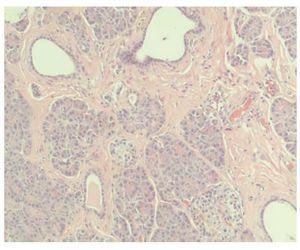

Hombre de 47 años de edad, sin antecedentes familiares o personales relevantes, con padecimiento de un día de evolución con dolor abdominal generalizado, vómito de contenido gastrobiliar y constipación. A la exploración física se encontró con FC 110 x', temperatura 38.5 °C, distensión abdominal importante, disminución de la peristalsis y signo de rebote presente. En los exámenes de laboratorio se encontró leucocitos de 10 700 / mm3, neutrofilia de 82% y bandemia de 7%. El paciente presentó deterioro clínico, con mayor distensión y dolor abdominal por lo que se decidió operarlo con diagnóstico probable de obstrucción intestinal. Se realizó laparotomía exploradora, encontrando torsión de un divertículo de Meckel ubicado a 60 cm de la válvula ileocecal, de 11 cm de longitud y 5.5 cm de diámetro, con pared de 0.3 centímetros de grosor (Figuras 1 y 2). Se encontraron datos de sufrimiento intestinal por lo que se realizó resección y anastomosis termino-terminal. En el examen microscópico, se observó un divertículo verdadero cubierto por mucosa normal del íleon, alternando con zonas de mucosa gástrica heterotópica (Figura 3). Las glándulas gástricas se encontraban rodeadas por linfocitos. En el fondo del divertículo se observó tejido pancreático heterotópico, compuesto por ductos, acinos e islotes de Langerhans de características histológicas normales (Figura 4). El paciente presentó evolución clínica satisfactoria en el postoperatorio y egresó sin complicaciones.

¿ Figura 3. Divertículo verdadero, cubierto por mucosa normal del íleon, alternando con zonas de mucosa gástrica heterotópica.